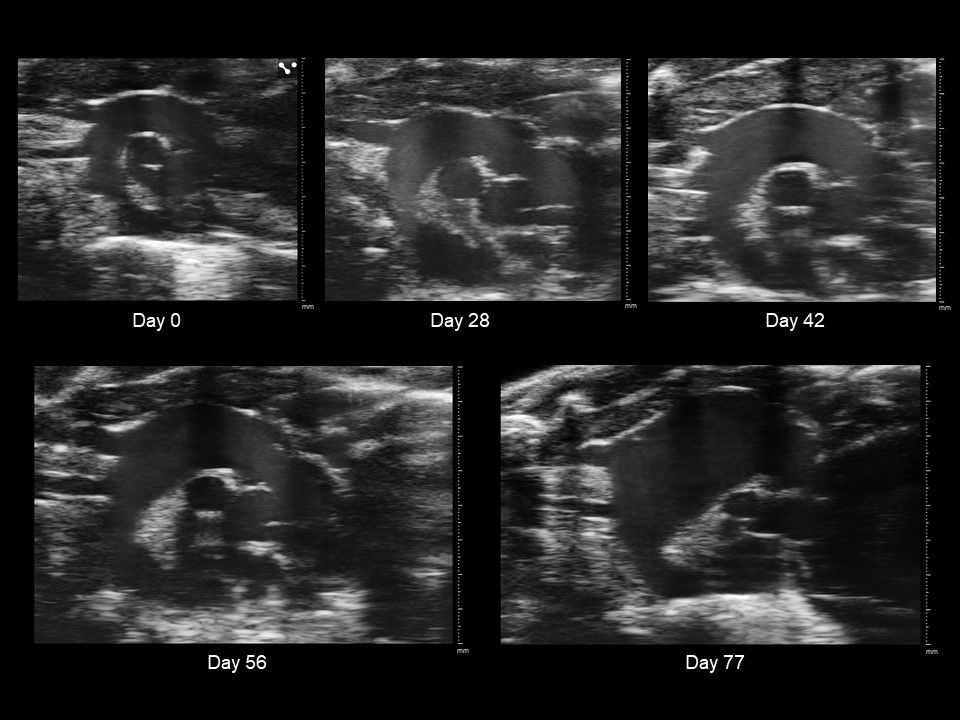

Progression of a Murine Thoracic Aortic Aneurysm

Caption: EKV ultrasound imaging visualizes the progression of a murine thoracic aortic aneurysm through five-time points after the introduction of BAPN (beta-aminopropionitrile) to drinking water. BAPN inhibits collagen replacement around major arteries, causing aneurysms when administered to young mice. Major tick marks indicate millimeters. Images were collected and processed with VisualSonics Vevo3100 and Vevo Lab.